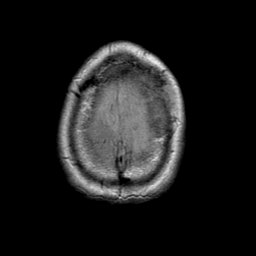

Meningioma, MR Study #1 -- Slice #20

[Home][Help][Clinical] Slice 20